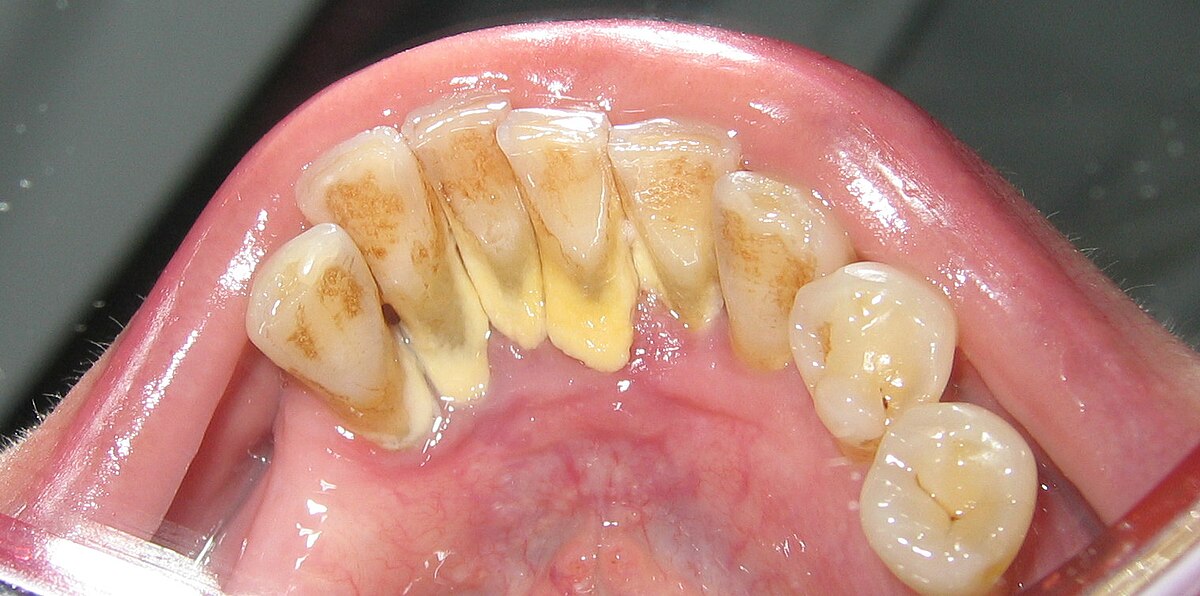

Before diving into the advanced technologies, it's essential to understand what it is. Calculus, commonly known as tartar, is a form of hardened dental plaque. When plaque is not removed through regular brushing and flossing, it can harden and form a rough, porous surface on teeth. This hardened plaque can build up to form a bridge-like structure across multiple teeth, known as a calculus bridge. This condition not only affects the aesthetics of the teeth but also contributes to gum disease, tooth decay, and other oral health issues.